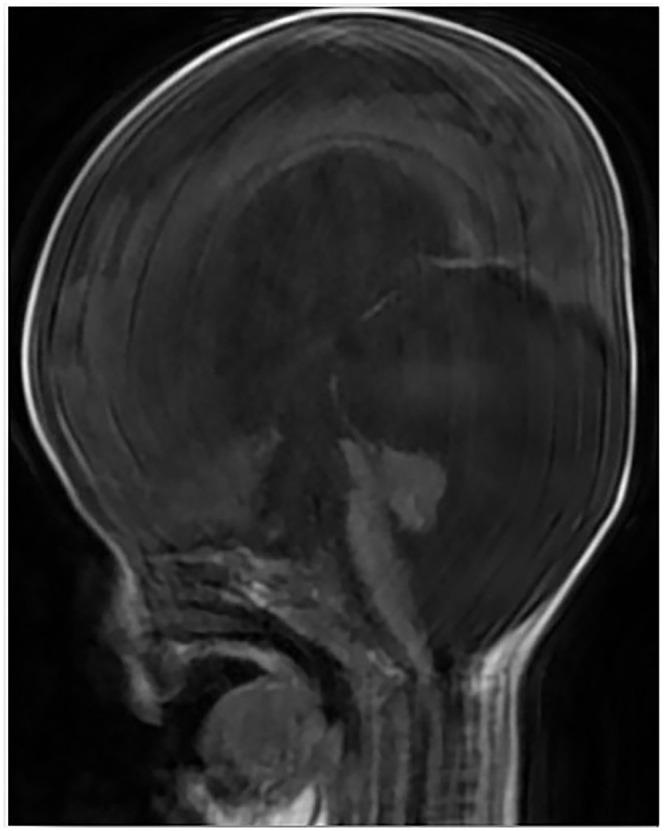

Dandy-Walker Syndrome (DWS) is a rare cerebellar malformation characterized by the underdevelopment of the cerebellar vermis and associated complications. This case report presents a 3-month-old female from Somalia who exhibited fever, loss of consciousness, vomiting, and developmental delays. Neurological examination suggested signs of meningitis, and MRI revealed an enlarged posterior fossa consistent with DWS. Despite initial antibiotic treatment for suspected bacterial meningitis, CSF cultures yielded no growth, raising concerns about prior antibiotic use. Unfortunately, the patient's condition deteriorated, leading to her death. This case highlights the diagnostic challenges of DWS in resource-limited settings and emphasizes the need for improved healthcare access, early diagnosis, and intervention for rare neurological conditions.